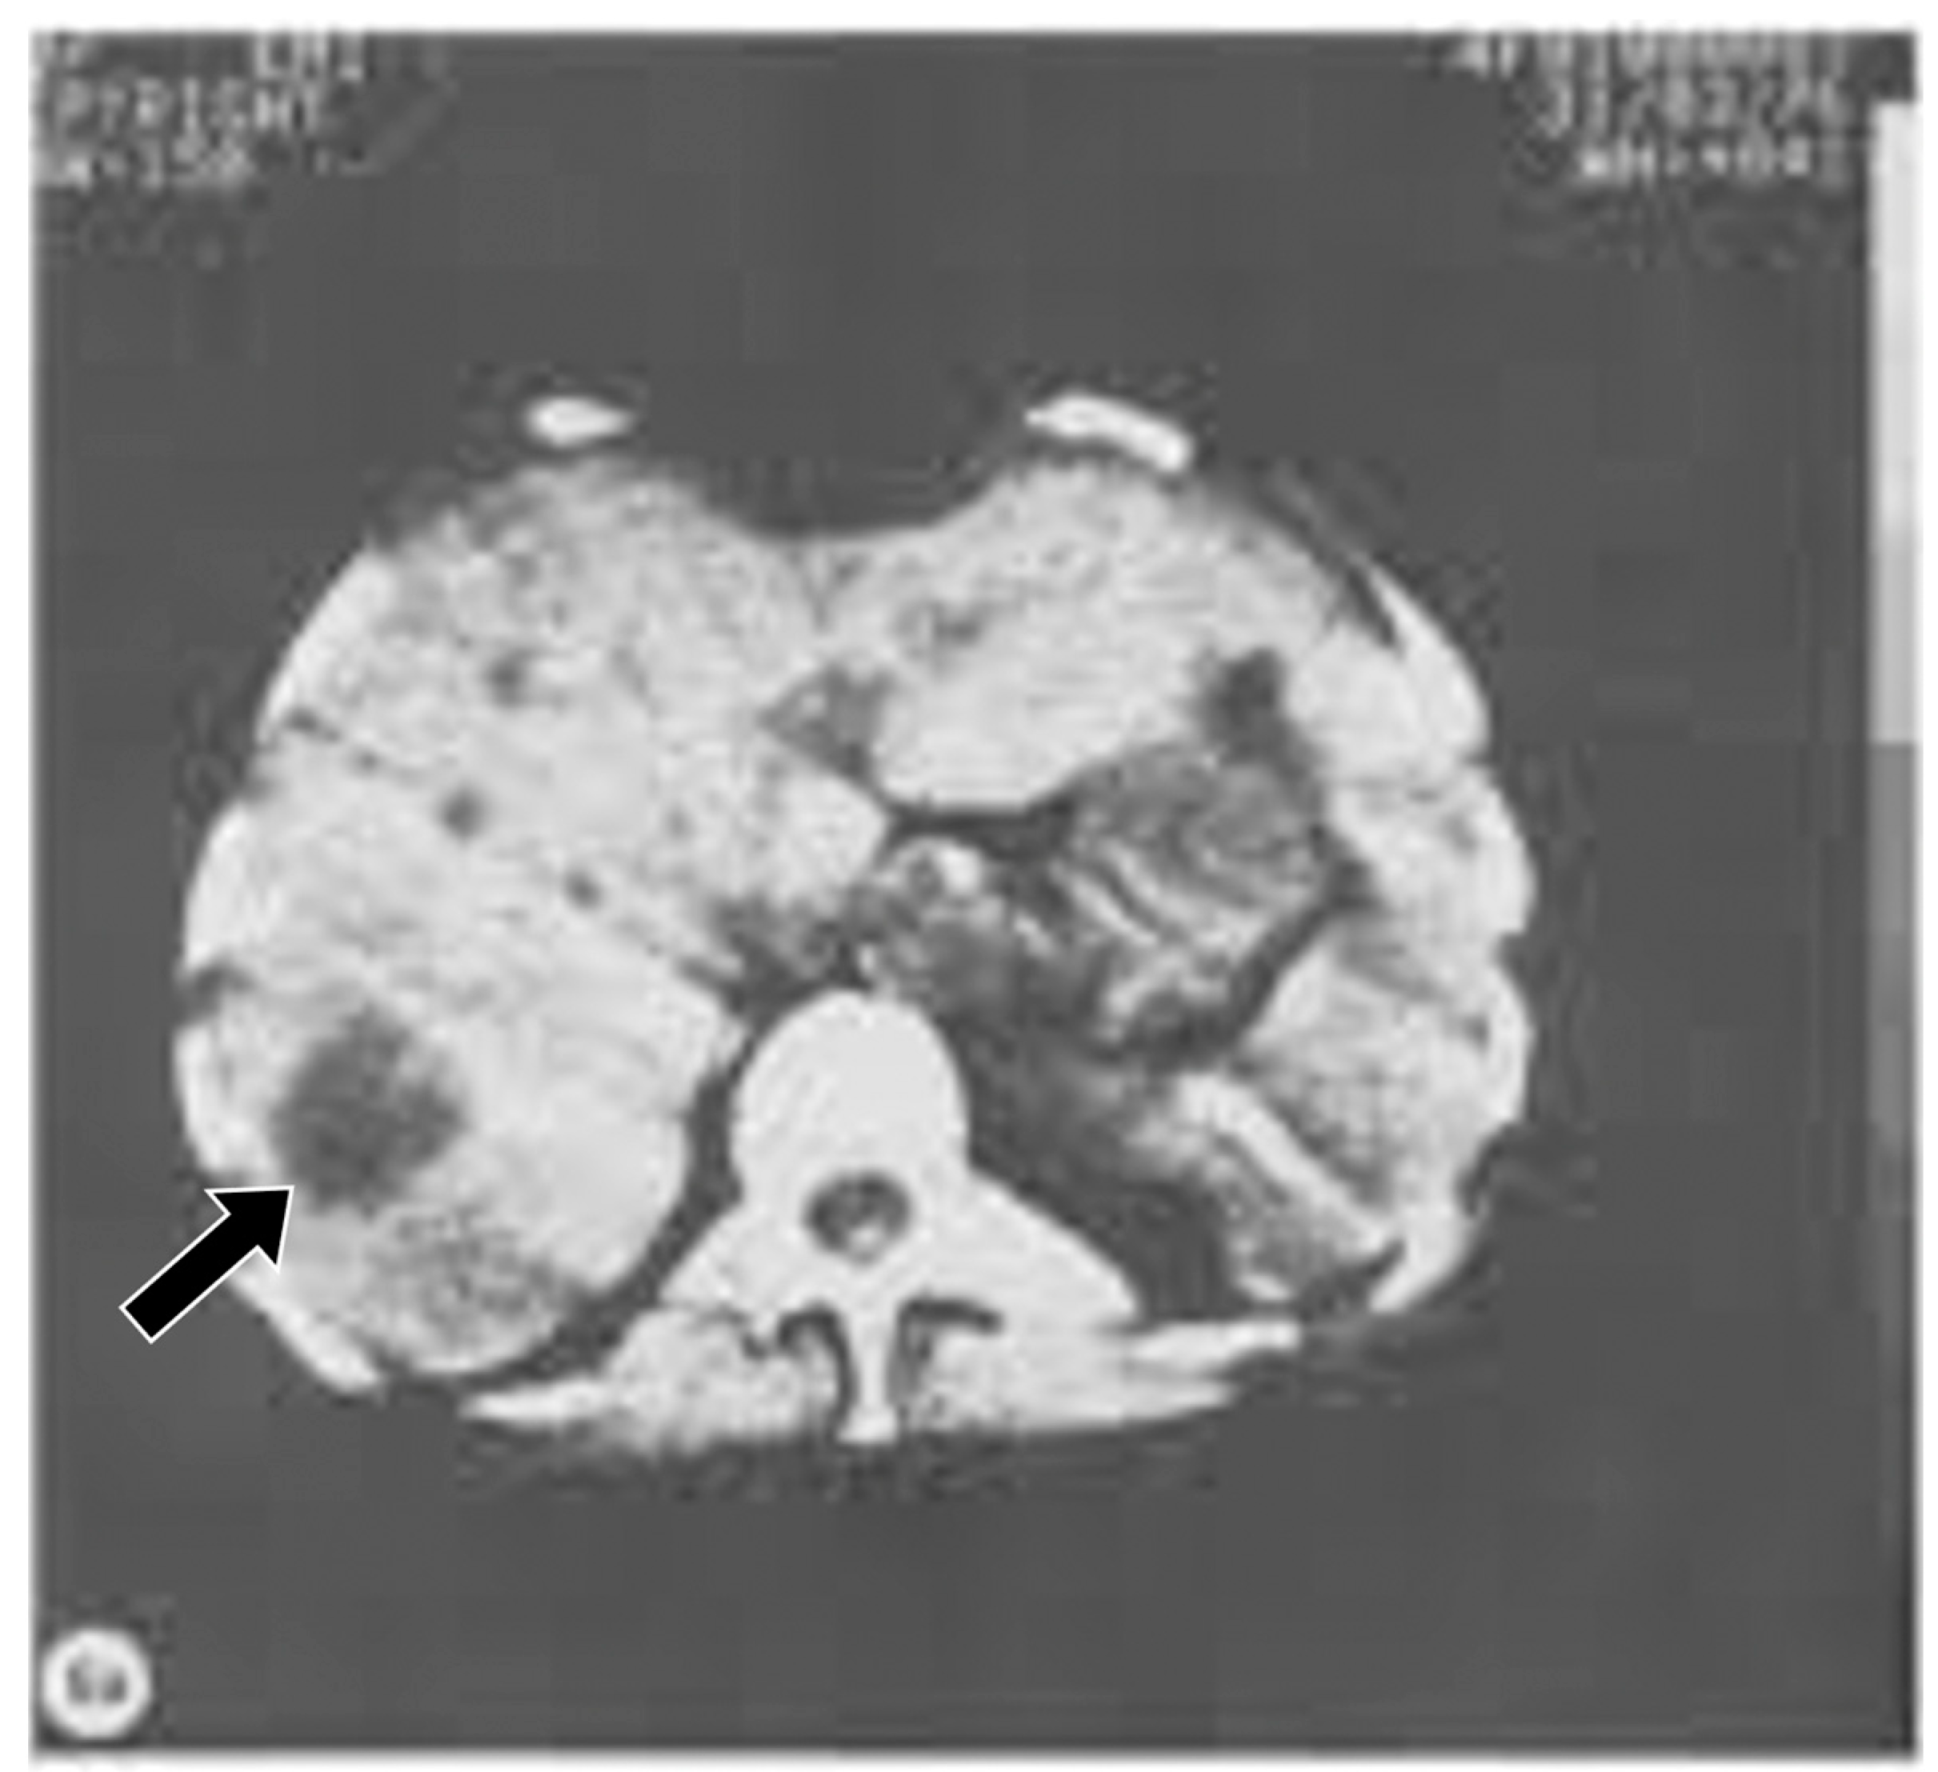

First patient examined with CT, frontal cystic glioma (October 1971) [5]. CT produced images of slices of the brain, which was a major improvement over conventional tomography. Signal is seen from the brain in this 80 × 80 matrix image. In addition, there is negative intrinsic contrast between the cystic glioma (black arrow) which is lower signal (darker) than the surrounding normal brain.

Figure 6.

Body CT transverse image of the liver (1976). The normal liver has a moderately high signal appearance. A tumor within the liver (black arrow) has a darker appearance. There is obvious negative intrinsic contrast between the tumor and the normal liver.